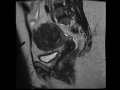

Adenomyosis

MRI imges demonstrates marked thickening of the junctional zone of the uterus, compatible with uterine adenomyosis.